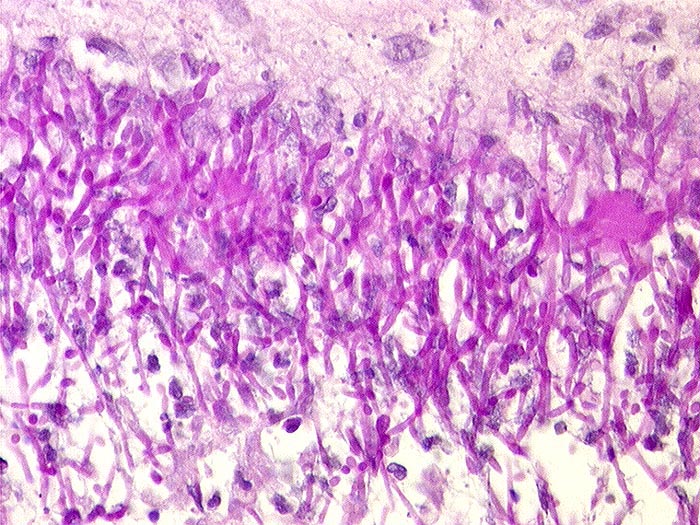

PathoPic ID 1462 - Soorösophagitis

Soorösophagitis

Entzündung infektiös

Oesophagus

PAS positive Soor Sporen (rund) und Pseudohyphen (Pilzfäden ohne echte Verzweigungen).

Histologie